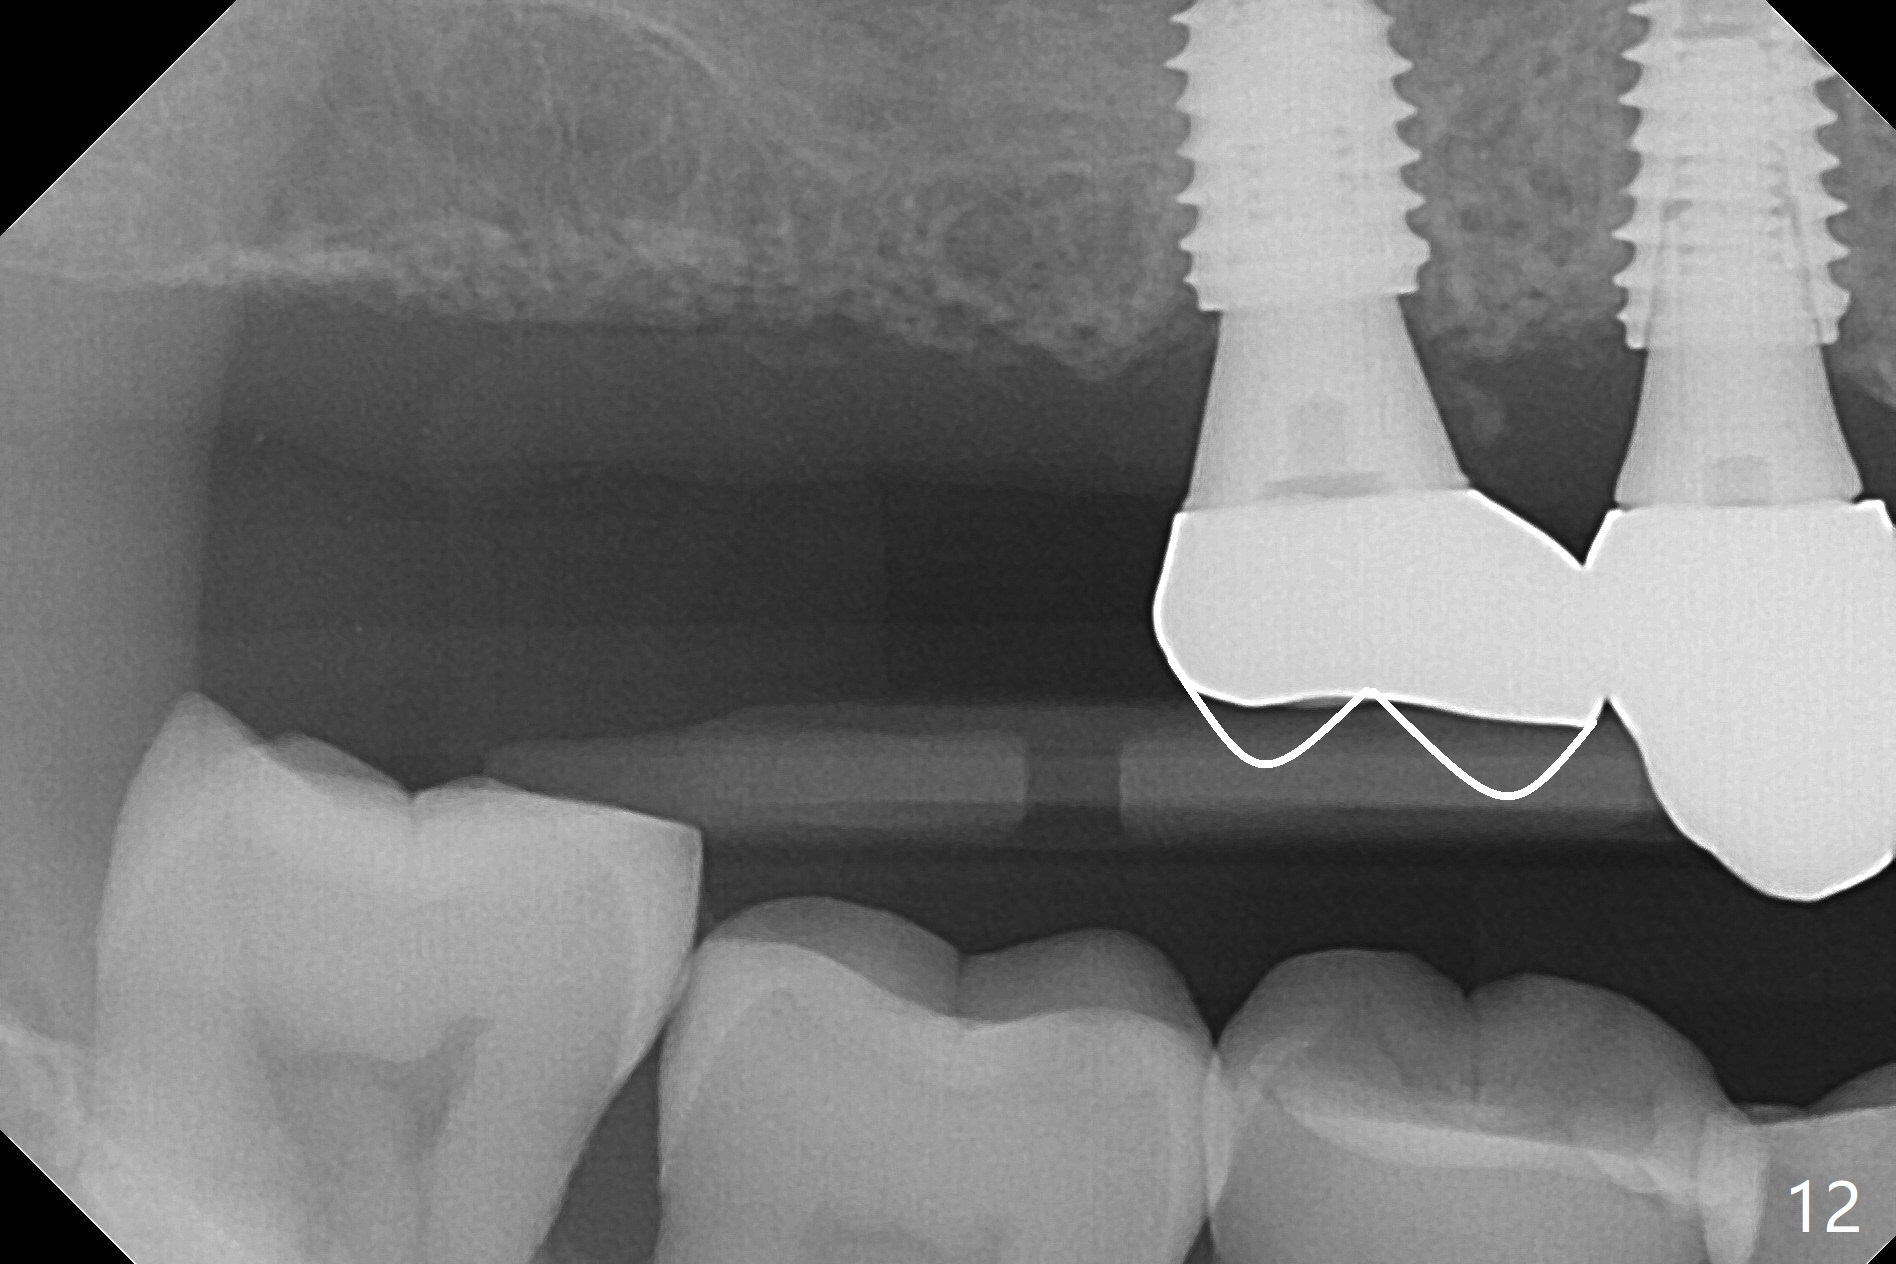

Osteotomy at #3 is performed last (Fig.1,2); as planned, a 4 mm cortical tap is used with guide for sinus lift. Unfortunately the sinus membrane is perforated. Implant placement is aborted. Instead Osteogen plug is inserted into the osteotomy, which is fixed in place by acrylic extending from the provisional at #4. Osteotomy for #3 implant will be attempted with control of the depth in 4 months. The patient has allergy to Amoxicillin (rash). When switching to Clindamycin, she develops diarrhea and loses 10 pounds. There is no abnormality at the site of #3 or 4 nearly 3 months postop (Fig.3). The next surgery will be most likely conducted without antibiotic 4 months postop. Try to draw blood for PRF. Take PA for #12 and 13 for possible impression. Remove the 3 temporary crowns, seat the guide across the arch and use no-stop fixture mounts at #4, and possibly 12 and 13. Follow the original drill sequence (check perforation after each drill, Fig.11) and use DIONavi sinus approach kit. Also load an appropriate stop for the round bur for sinus lift before hand. Mixture allograft with Metronidazole and PRF. In fact everything goes on as smoothly as planned. Osteotomy at #3 is underprep (3.5 mm in diameter drill instead of 4.0). The sinus floor appears to remain to be absent; 3.2 mm round bur is used for lift, alternating with water pumping. Following insertion of 3 pieces of PRF membranes and Vanilla Graft (Fig.4 *), a 4x10 mm dummy implant is placed. After additional bone graft (Fig.5 *), a final 4.5x7.3 mm implant is placed ~10 Ncm. The implant is placed deeper ~ 1 mm, followed by a 5.5x3 mm healing abutment (Fig.6). The implants at #12 and 13 seem to have osteointegrated (Fig.7). Impression is taken for #4, 12 and 13 with limited vertical space (Fig.8,9). An implant at #14 is being considered. There is faint bone graft around the apex of the implant 4 months postop (Fig.10). The implant sustains 25-30 Ncm torque when a 5.2x4(3) mm cemented abutment is placed. A permanent crown is cemented nearly 5 months postop (Fig.11). For the best cosmetic and masticating results, the occlusal surface should have certain degree of morphology, such as the buccal cusps (Fig.12 white curved lines). The abutment at #3 is placed and torqued to 30 Ncm before re-cementation of the repaired crown (increased occlusal surface contact). In fact the abutment at #4 is incompletely seated with a gap (Fig.13 <). The composite at #5 is dislodged while #3 crown is being repaired (*). The abutment at #4 is loose >1 year post cementation. The abutment remains incompletely seated (gap and longer apical space (double arrows)) when the abutment/crown complex rotates lingual mesiobuccal (Fig.14 curved arrow). Further proximal reduction and lingual rotation distobuccal leads to complete seating (Fig.15). It appears that incomplete seating at #13 is associated with hex mismatch (Fig.16, large apical space), which will be fixed next visit. One week later, the crown and abutment of #4 are seated together after crown repair (Fig.17). Since the abutment margin is subgingival, the crown is cemented, removed with abutment for residual cement removal and reseated with the abutment with torque at 30 Ncm. After this, the crown and abutment of #13 is reseated after mesiobuccal surface is trimmed (Fig.18), followed by pick up impression. A few days later, the crown/abutment are inserted together smoothly, the former cemented and the complex unscrewed for residual cement removal and last torqued at 30 Ncm without any X-ray confirmation.